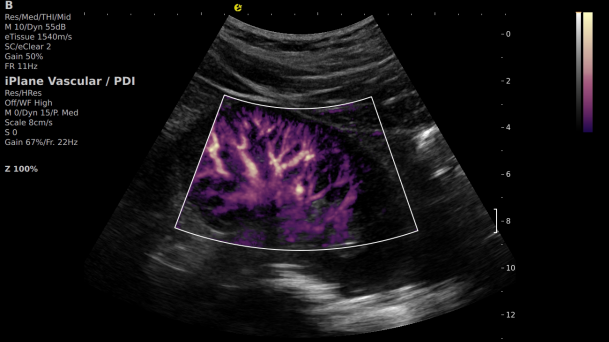

在肾移植领域,医生最怕的不是手术刀下的惊心动魄,而是那些手术后肉眼看不见的危机——急性排斥反应导致的血小板聚集形成的微血栓、毛细血管网损伤等...这些“隐形杀手”曾让无数移植肾在悄无声息中衰竭。而银河官网医疗(ESI)的iPlane Vascular平面波超微细血流显像技术,正是为破解这一难题而生。

这项革命性技术通过三大创新实现质的飞跃:

1) 基于OmniSound?平面波超快速平台,超声信号采集帧频提高了200倍(25000Hz)。

2) 可检测20-50μm级细小血管低速血流信号,能看清头发丝1/2粗细的微血管;

超微视血流显像显示肾脏五级血管